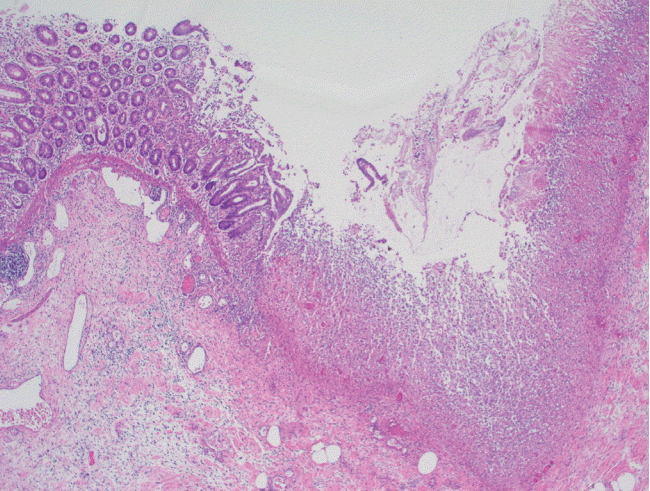

She underwent a second colonoscopy which showed mild patchy colitis throughout the colon with rectal sparing (Fig. 1). Biopsy revealed patchy mild active chronic colitis. There were rare small clusters of histiocytes without well-formed granulomata (Fig. 2).

Fig. 2.

H&E stained slides from colonic biopsies (×200). The section shows mildly active colitis with increased mixed inflammatory cells in the lamina propria and an occasional cluster of histiocytes beneath the surface epithelium.